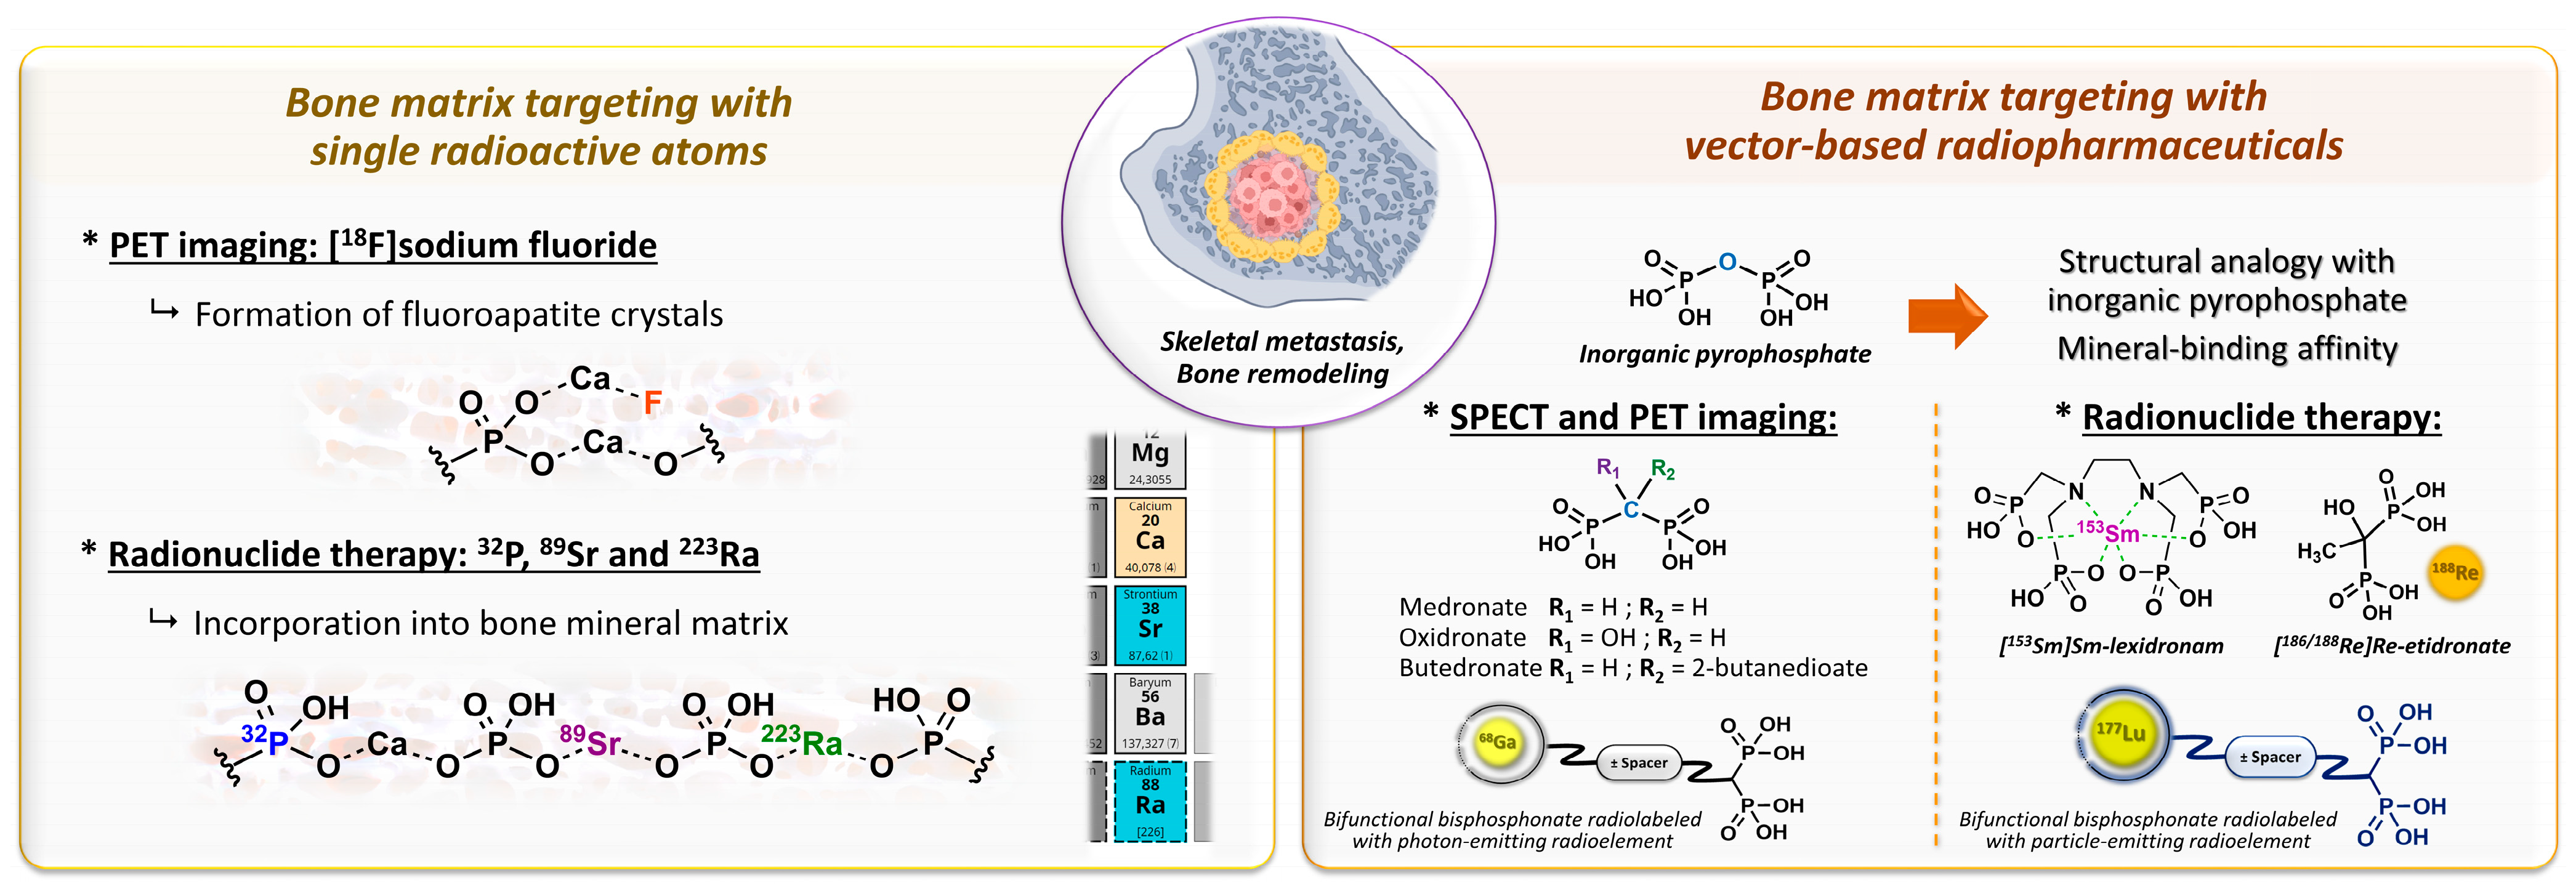

2.2. Bone Metastases Molecular Targeting and Early Bisphosphonate-Based Radiopharmaceuticals

- Specific bone targeting based on the electronic properties of a free radioactive atom: two isotopes of the same atom do not differ in their electronic structure and therefore have identical chemical properties, which allows skeletal targeting by the isotopes of atoms with natural affinities for bone. This applies to [18F]fluoride ions, which replace hydroxide anions in hydroxyapatite crystals to form fluoroapatite in the bone mineral [82]. The [18F]NaF PET imaging agent tends to be more accurate than bone scintigraphy for the detection of skeletal metastatic lesions in several types of cancer [83,84,85,86]. In therapy, [32P]orthophosphate (t1/2 = 14.3 days; Eβ-max = 1.71 MeV) is also incorporated into hydroxyapatite crystals [87] and was historically used to treat painful osteoblastic metastases [88]. This treatment showed moderate efficacy with the disappearance of pain symptoms in almost half of patients [89] but caused common bone marrow toxicity, especially in patients with renal impairment. Likewise, the chemical elements in the same group/column of the periodic table of elements are characterized by the same number of valence electrons, and therefore, by usually comparable chemical reactivity. Part of the same group as calcium, 89Sr (t1/2 = 50.5 days; Eβ-max = 1.49 MeV) is an alkaline earth metal that accumulates in lesions with high osteoblastic activity and has been used under its dichloride salt form in the palliative treatment of pain associated with bone metastases [90], especially in prostate cancer. The initial clinical trials with this radiopharmaceutical in monotherapy showed modest effects on pain control in bone metastases associated with substantial bone marrow toxicity [91,92,93], while its use in patients treated with doxorubicin [94] or docetaxel [95] tended to improve both the symptoms associated with bone metastases and survival. Similarly, alpha-emitting radionuclide 223Ra (t1/2 = 11.4 days; Eα = 5.0 to 7.5 MeV [95.3%]; Eβ-max = 1.37 MeV and 1.42 MeV [3.6%]) showed an overall survival benefit in patients with metastatic prostate cancer, with a significant 9-month delay in bone-related events when associated with a bone-protecting agent (e.g., denosumab) [96]. To date, radium-223 dichloride (Xofigo®, Bayer, Leverkusen, Germany) is the only FDA- and EMA-approved targeted alpha therapy available.

- Specific targeting based on a vector molecule with bone tropism: in scintigraphic imaging, medronate (MDP) [97] and oxidronate (HMDP) [98,99] were among the first bisphosphonates to be used as bone scintigraphy imaging vectors on humans after the pioneering application of [99mTc]Tc-etidronate [100,101,102,103] (Figure 5). These two compounds are characterized by their simple chemical structures, which do not contain dedicated chelation sites. Although their formulation in single-vial cold kits for radiopharmaceutical preparation makes 99mTc radiolabeling simple and ensures high radiochemical purity levels, [99mTc]Tc-MDP and [99mTc]Tc-HMDP complexes do not form a single defined chemical entity but are rather structured into a mixture of monomers, oxo-bridged dimers and oligomeric clusters of varying sizes, featuring diverse technetium-oxo core arrangements, oxidation states and ligand coordination numbers [104] with a composition that varies according to pH, technetium concentration and oxygen amount [105]. Lastly, the phosphonate groups of MDP and HMDP (as well as the hydroxyl group of HMDP) serve both as coordination sites with 99mTc and as recognition sites for the bone mineral matrix. Consequently, the bone affinity of the corresponding 99mTc complexes is intrinsically reduced [106]. Even so, these radiopharmaceuticals remain reference bone scintigraphy agents, either in oncology for cancer staging [107,108] and therapeutic response evaluation [109,110,111] or in benign bone disorders such as Paget disease [112,113] or primary hyperparathyroidism [114,115]. Interestingly, 99mTc-radiolabeled butedronate (2,3-dicarboxypropane-1,1-diphosphonate, DPD, Figure 5) [116] is another SPECT imaging agent with the same indications as [99mTc]Tc-MDP and [99mTc]Tc-HMDP but also has a particular role in the detection of cardiac amyloidosis [117,118,119]. Concerning therapy, a bisphosphonate-related derivative with an ethylenediamine tetraphosphonate structure (EDTMP, also named lexidronam) radiolabeled with 153Sm (t1/2 = 1.9 days; Eβ-max = 0.81 MeV) has also been used since the late 1980s [120,121] for the relief of pain resulting from bone metastases; two clinical trials demonstrated its efficacy in this indication versus the placebo and its improved toxicity profile compared to 89Sr and 32P [122,123]. Notably, etidronate was also selected for radionuclide therapy applications after radiolabeling with beta minus-emitting rhenium isotopes, either 186Re or 188Re [9,10,11,12,13,14,15,16,17,18,19,20,21], but with rather limited clinical use.